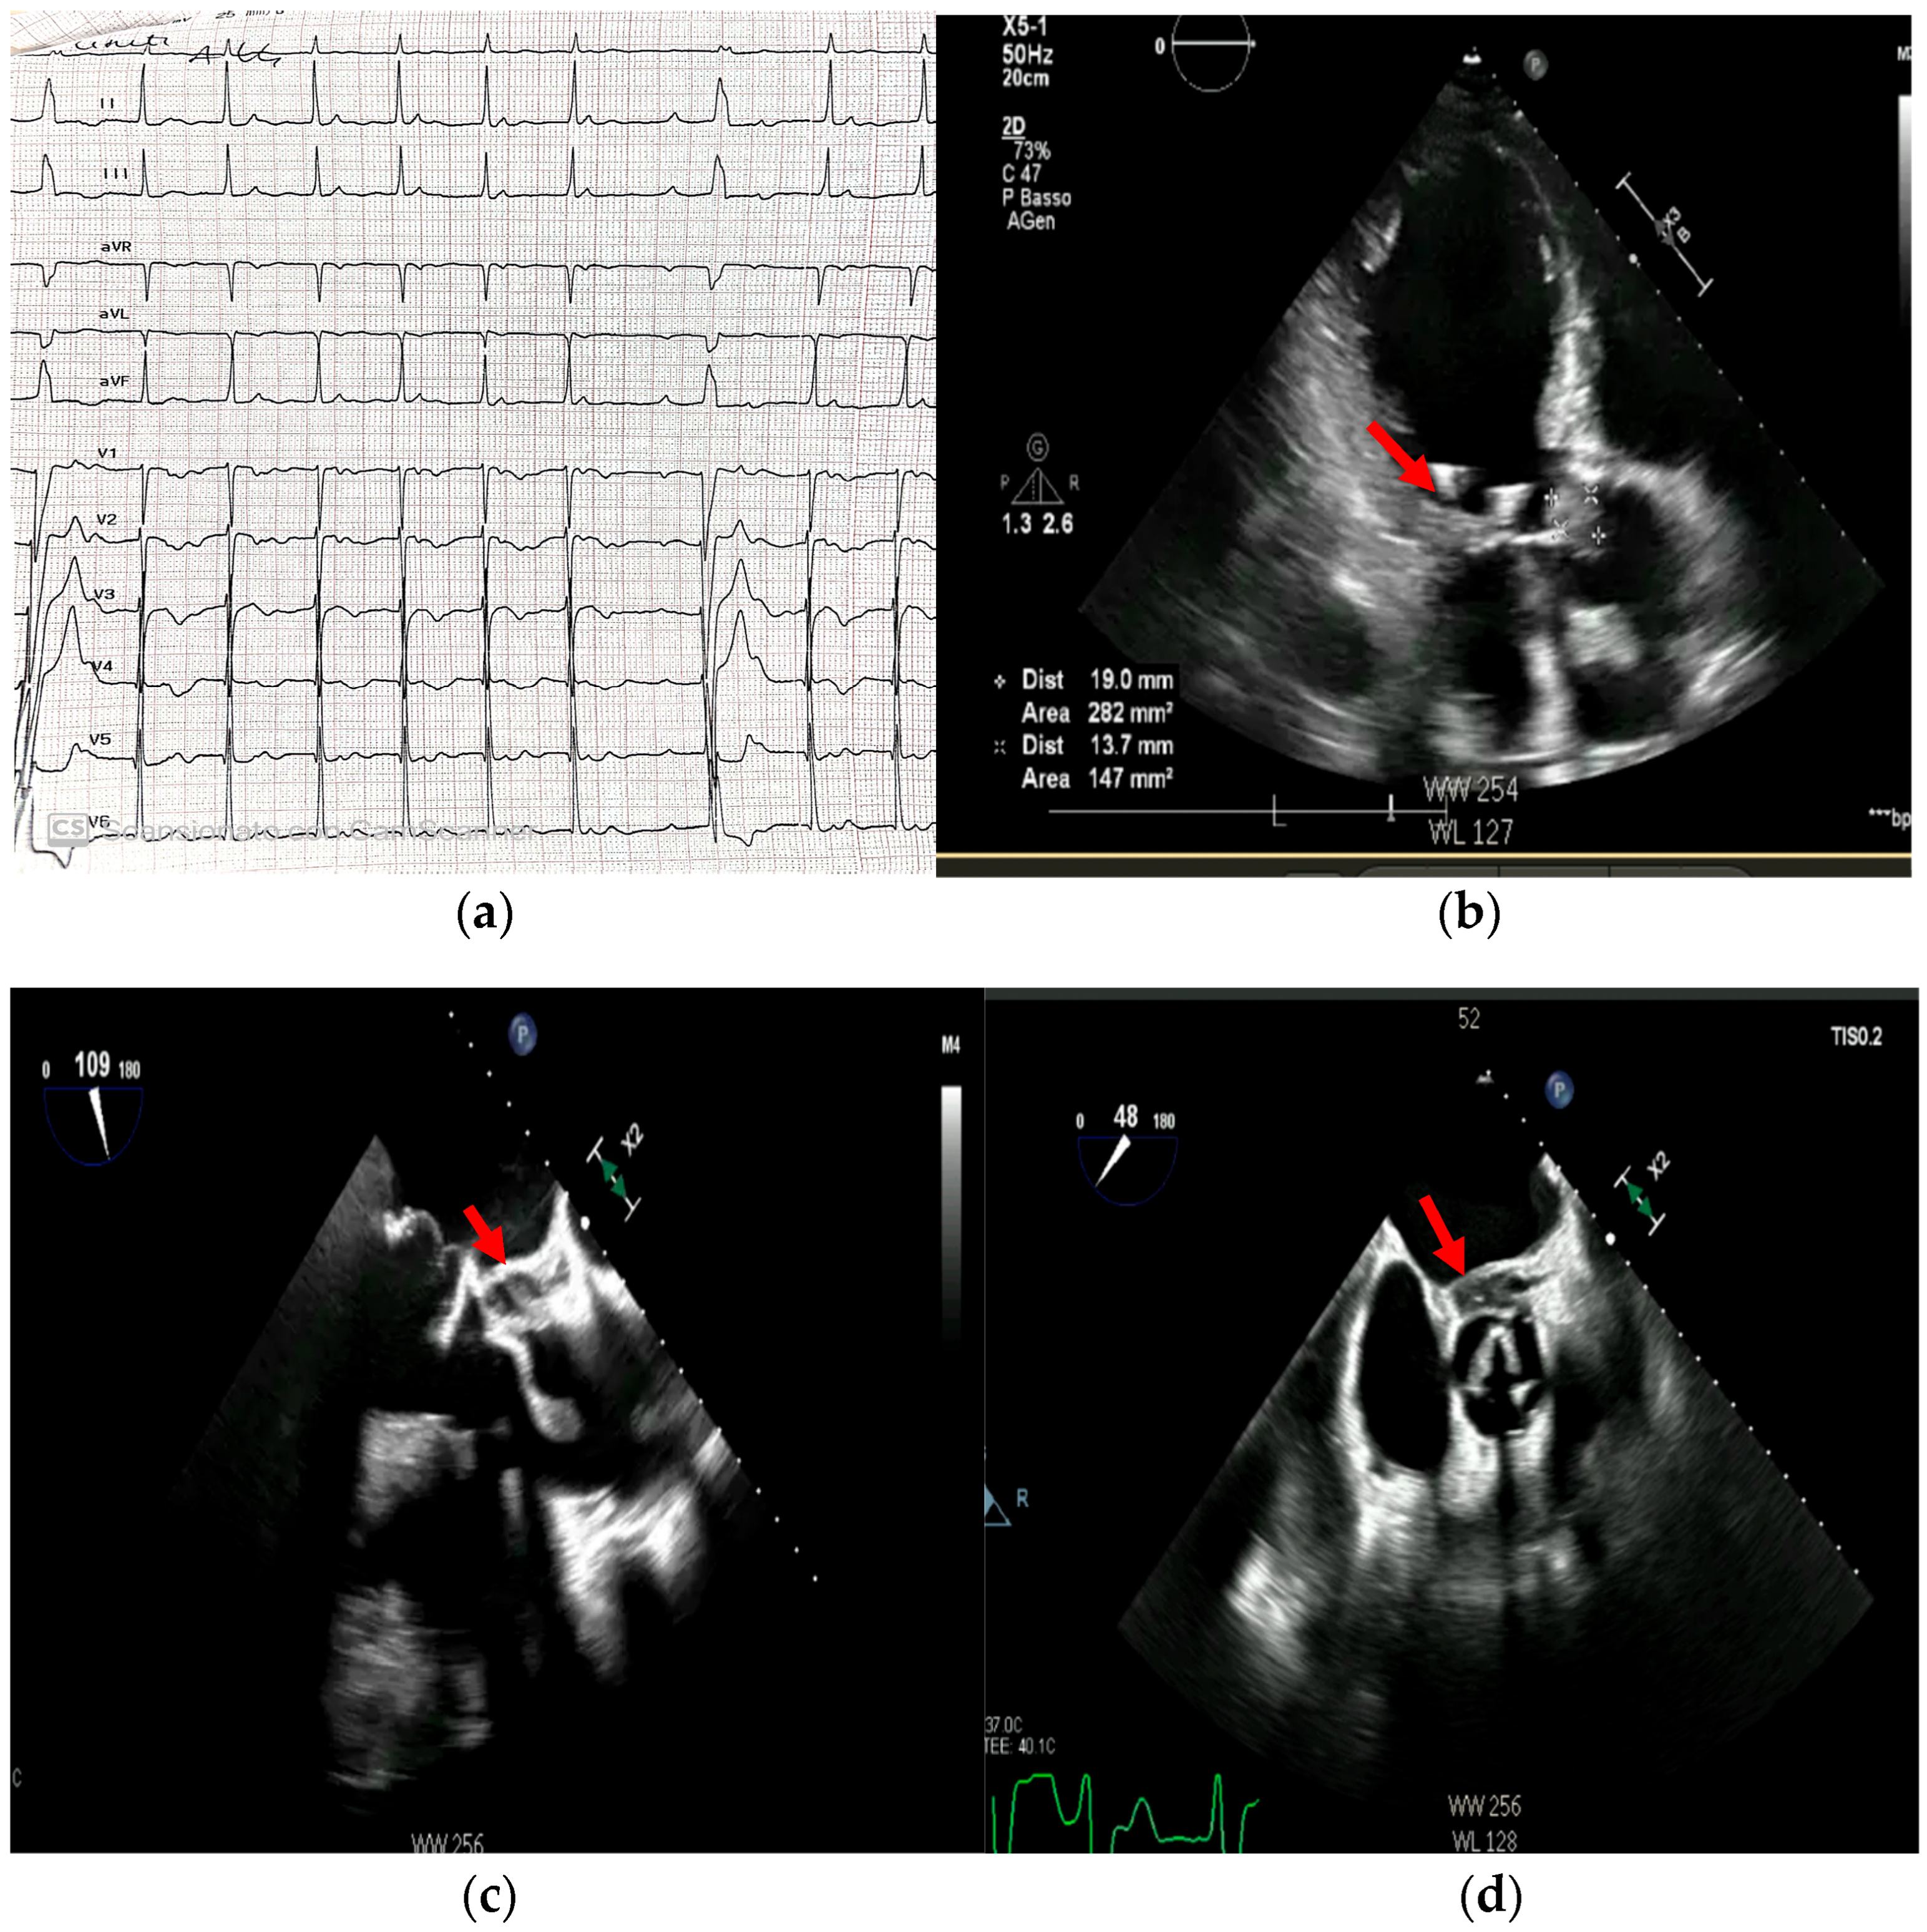

4. Echocardiography

- valvular or leaflet perforation, i.e., tissue defects causing valvular regurgitation originating from the site of perforation.

- valvular aneurysm, a saccular outpouching of a valve leaflet, protruding into the atrium or ventricle.

- perivalvular or perigraft abscess, an echolucent or echodense area adjacent to the valve annulus or prosthetic ring often with irregular borders and sometimes with evidence of cavity formation.

- pseudoaneurysm, a contrast-filled outpouching with a narrow neck communicating with the cardiac lumen, often adjacent to the valve annulus. On echocardiography, it appears as a pulsatile cavity with systolic expansion and diastolic collapse.

- intracardiac fistula, visualized as an abnormal communication between cardiac chambers or vessels, is often detected by using color Doppler.

- significant new valvular regurgitation compared with previous imaging, i.e., increase in regurgitant jet size, vena contracta width…